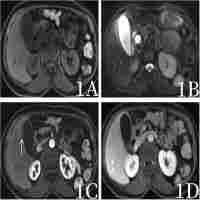

| Abstract | Inflammatory pseudotumors are rare benign tumors consisting of cellular and stromal elements of a localized reactive process. While inflammatory pseudotumors are commonly detected in the lung and occasionally in other organs, only one case of inflammatory pseudotumor of the thymus has been reported in the literature to date. This report presents a 54-year-old male patient with inflammatory pseudotumor of the thymus accompanied by pulmonary inflammation. The patient presented with chest pain and moderate fever for 12 days. Enhanced computed tomography of the thorax revealed an anterior mediastinal solid and cystic mass, which constricted the left brachiocephalic vein accompanied by bilateral lung inflammation and marginal pleural effusion. The patient underwent a median sternotomy for the surgical removal of the mass. Histologically, the resected mass was composed of necrotic and fibrous tissues and inflammatory infiltrates, and the diagnosis was confirmed as an inflammatory pseudotumor of the thymus. The patient’s symptoms were resolved following surgery and the patient remained asymptomatic during the six-month follow-up period. In addition, we reviewed the previous literature and discussed the diagnosis and management of our patient. This report provides further insights into the pathogenesis and underlying mechanisms of inflammatory pseudotumors of the thymus to aid in the diagnosis and development of effective therapies. |